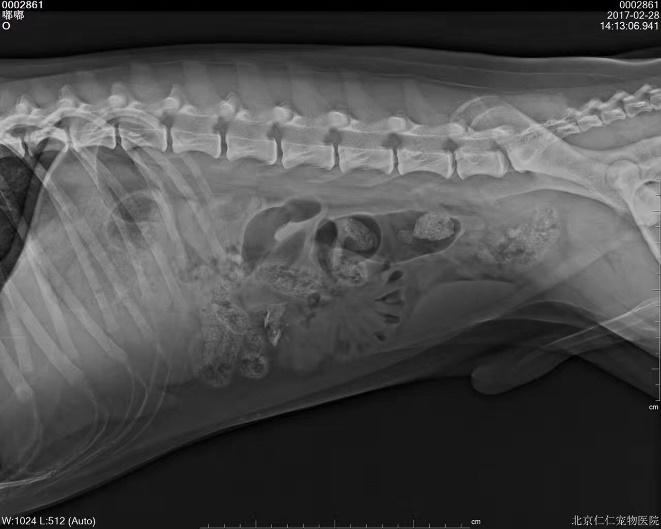

b. X射线检查:针对阻线性较强的物质(如金属、骨头)较容易辨别,针对阻线性与组织密度相似的物体较难确定,但是可以通过消化道灌服造影剂判断是否有阻塞或可包裹物体。

胃的正常大小:胃位于前腹部,隔和胆脏之后。胃排空时位于肋弓以内;从腹底算起,胃的腹侧缘大约在腹腔深度的1/3处。胃充盈时,胃向后向下延伸,与横结肠和腹底部相接。

摆位对

胃内异物(金毛,手术取出6cm大衣扣子)

钡餐4小时后胃内未排空(家猫,线性异物)

c.X线检查。针对阻线性较强的物质(如金属、骨头)较容易辨别,针对阻线性与组织密度相似的物体较难确定,但是可以通过消化道灌服造影剂判断是否有阻塞或可包裹物体。

机械性肠梗阻的读片要点:1.体积增大;2.形态轮廓变化;3.影像密度变化;4.浆膜细节变化。

金毛 线性异物